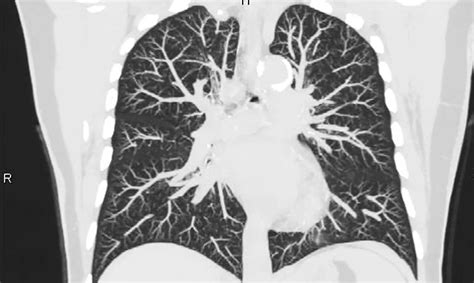

Per una corretta diagnosi, oltre alla TAC torace, può essere necessaria una broncoscopia per escludere altre patologie, come infezioni (ad esempio, la tubercolosi). In caso di emorragia alveolare, il lavaggio broncoalveolare (BAL) rivelerà liquido ematico. Sono raccomandate visite otorinolaringoiatriche e studi approfonditi sulla funzionalità renale. Gli esami del sangue possono rivelare indici di infiammazione aspecifici (VES, PCR) e la presenza di autoanticorpi specifici denominati ANCA (in particolare cANCA), utili ai fini diagnostici se interpretati nel contesto clinico e radiologico.

La diagnosi si avvale di test di funzionalità polmonare (PFT) che misurano la capacità polmonare e lo scambio gassoso, e TAC ad alta risoluzione. La biopsia polmonare può essere necessaria per confermare la presenza di fibrosi e determinarne la causa.

Un segno radiologico costante in tutti i casi di bronchiolite, visibile alla TAC torace ad alta risoluzione (HRCT), è l'"albero in fiore" ("tree in bud sign"). Questo si manifesta come micronoduli centrolobulari connessi a strie lineari arborizzate, rappresentanti i bronchioli interessati dal processo patologico, riempiti da secreto muco-purulento e cellule infiammatorie.

Una diagnosi tempestiva, supportata da indagini strumentali come la radiografia del torace e la TAC, insieme a test di funzionalità polmonare, è fondamentale per un trattamento efficace. La collaborazione tra pazienti e personale medico è essenziale per monitorare la progressione della malattia e adattare le terapie, migliorando la qualità della vita e, quando possibile, rallentando l'inarrestabile decorso di alcune di queste patologie.